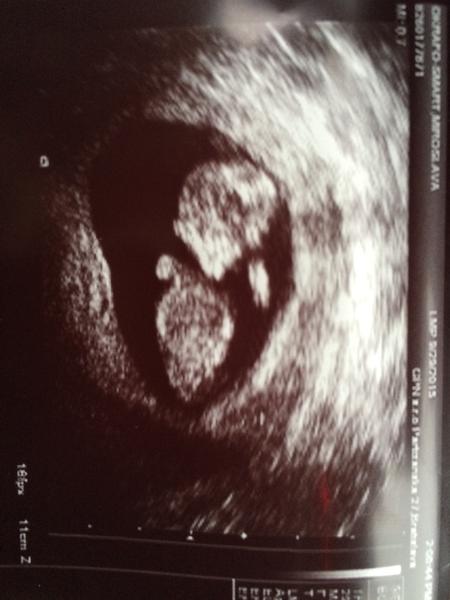

@sara34valentina na mojej foto si sa pipika nedopatrala lebo akurat iva zadocek otrcil drobec 😀

ABaby popika este nevidiet 🙂 ale drobciatko sa krasne mrvilo a otacalo v bruchu a chytalo sa za hlavu, videla som mu nohy a vsetko mozne, drobciak zodpoveda 11+2.